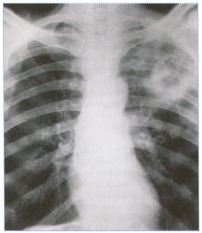

Diagnosis of active TB relies usually on chest X ray, as well as microscopic examination and microbiological culture of body fluids.

- Chest Xray

Patients with active pulmonary tuberculosis are usually advised to stay at home or be admitted to a hospital for 2 weeks at the initial period to avoid spreading the disease to others. Symptoms often improve in 2 – 3 weeks but chest x-ray improvement usually lags behind.